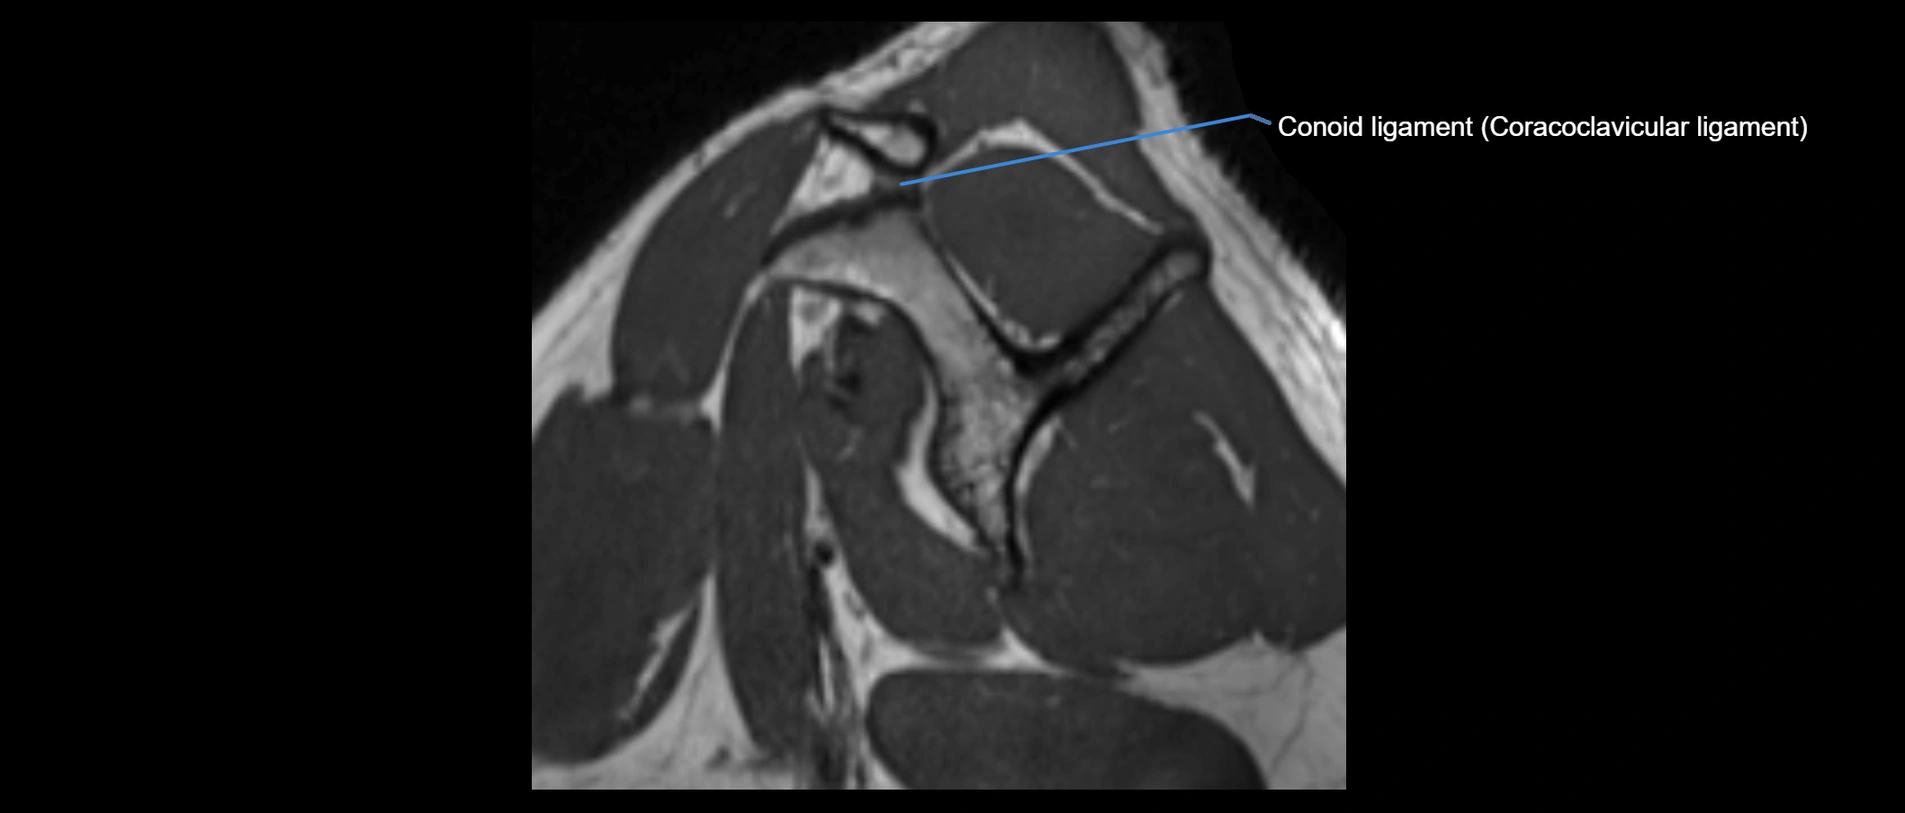

MRI images

image